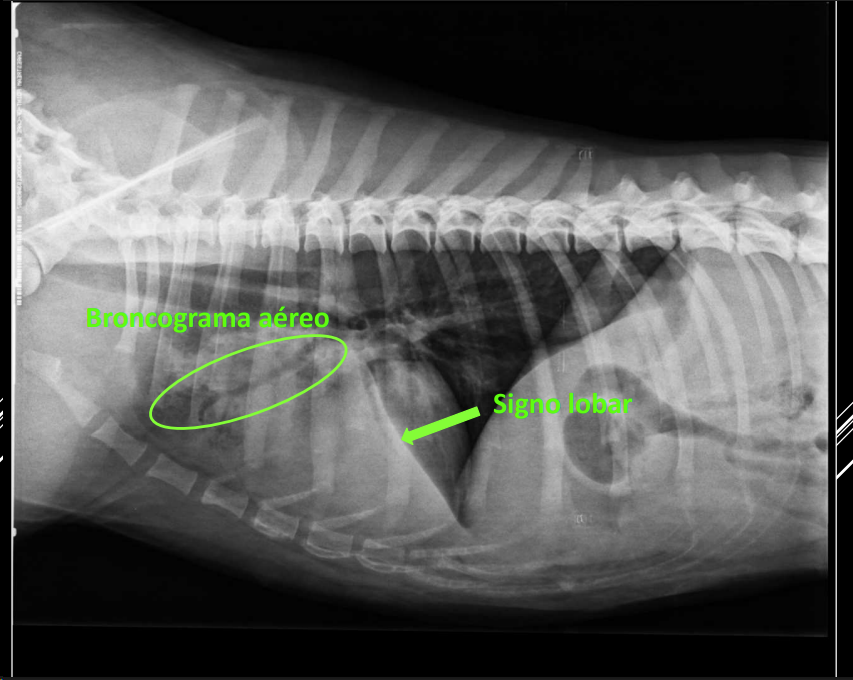

PATRÓN ALVEOLAR

- Opacidad homogénea.

- Broncogramas aéreos visibles (patognomónicos).

- Signo lobar (borde visible entre lóbulos) cuando hay un lobulo sano y otro que no lo está.

- Patognomonico de patron alveolar cuando vemos los bronquios oscuros alrededor de blanco. No siempre ocurre (cuando hay moco no se ocurre) se llama broncograma aereo.

Por consolidación: edema, neumonía, hemorragia, neoplasia.

Por atelectasia: obstrucción, compresión, neumotórax, efusión pleural.